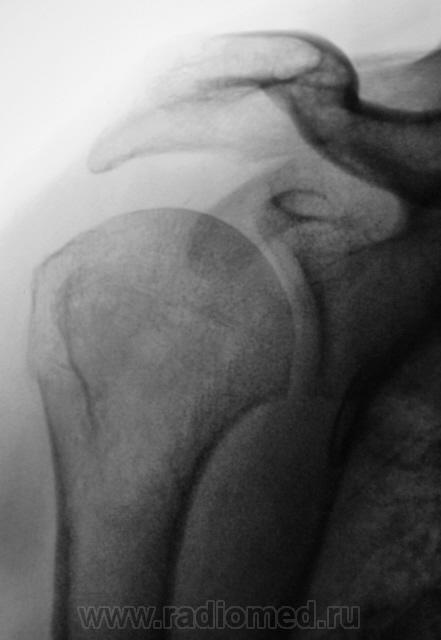

Сегодняшний случай.

1..H.P..JPG2..H.P..JPG3..H.P..jpg